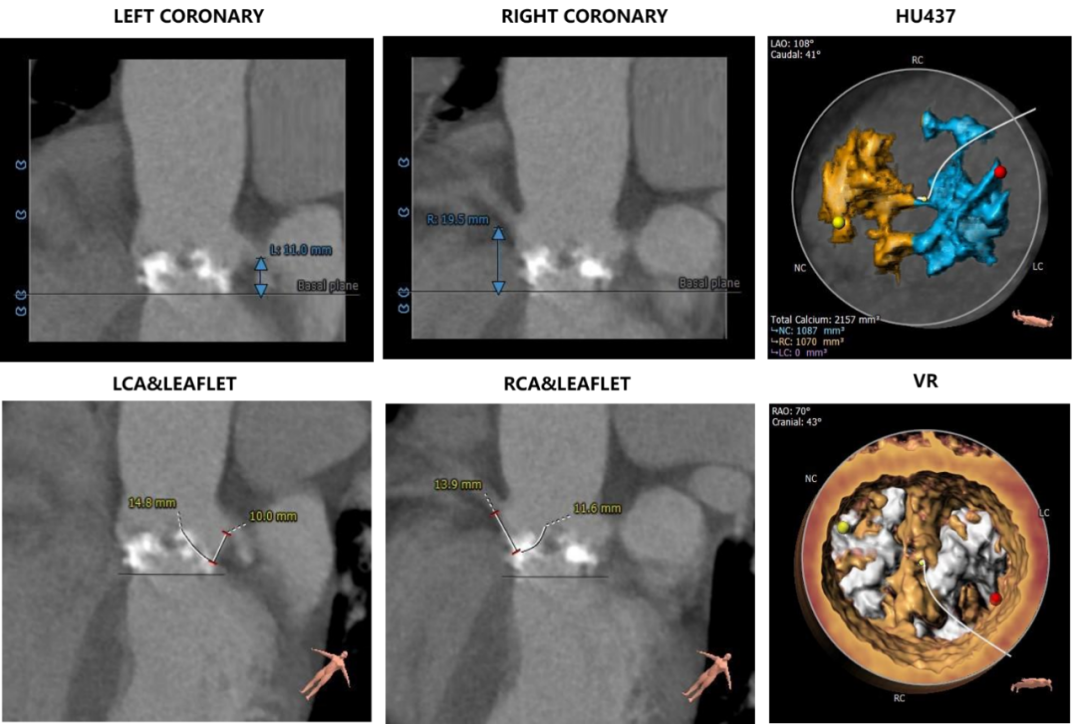

Type0型二叶式主动脉瓣,瓣叶中度钙化并纤维增厚,钙化似云雾状分布于两侧瓣叶。

左冠开口高度稍低,左冠瓣长度偏长。

非横位心,主动脉弓角度与宽度合适。入路血管局部钙化,双侧血管内径良好,整体入路血管条件较好。

主动脉根部测量

冠脉风险评估

瓣环上结构评估

外周血管及主动脉弓解剖

该急诊患者影像质量欠清晰,另该患者体位非平卧,给术中投照角度确定带来一些挑战。瓣叶上的钙化预估对人工瓣膜形态影响较大,存在根部损伤及瓣周漏较大可能,大概率需要做后扩张。

冠脉开口高度稍低,左冠瓣瓣叶偏长,综合瓦氏窦内径等因素考虑,有一定冠脉遮挡风险,术中可借助食道超声测量钙化到左冠开口的距离以及评估冠脉血流,再决定是否行冠脉保护。

手术策略方面,综合考虑瓣环及瓣环上结构,选用20mm球囊预扩张,预装TaurusOne AV26瓣膜,在瓣环下0-2mm偏高位释放。